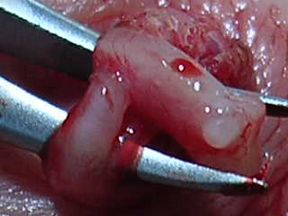

Of the four patients on whom I performed the VasClip procedure in the presence of the founder of the company, two experienced early failure. This 50% early failure rate is not acceptable and I no longer perform the VasClip procedure. The other two patients became sperm-free, but they are aware of the other two early failures and they have been encouraged to have their semen checked periodically for the delayed reappearance of sperm (late failure). The photos below were taken during the repeat vasectomy (on 2/23/05) of a man who had experienced VasClip failure.